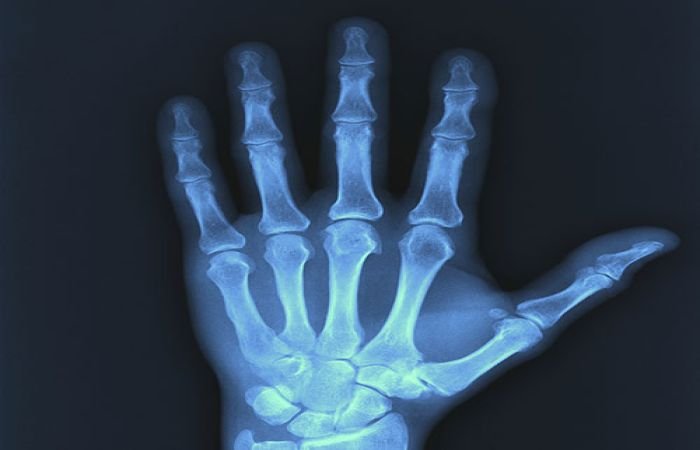

- Medical Imaging

- Used in radiography and CT scans to visualize bones and internal organs